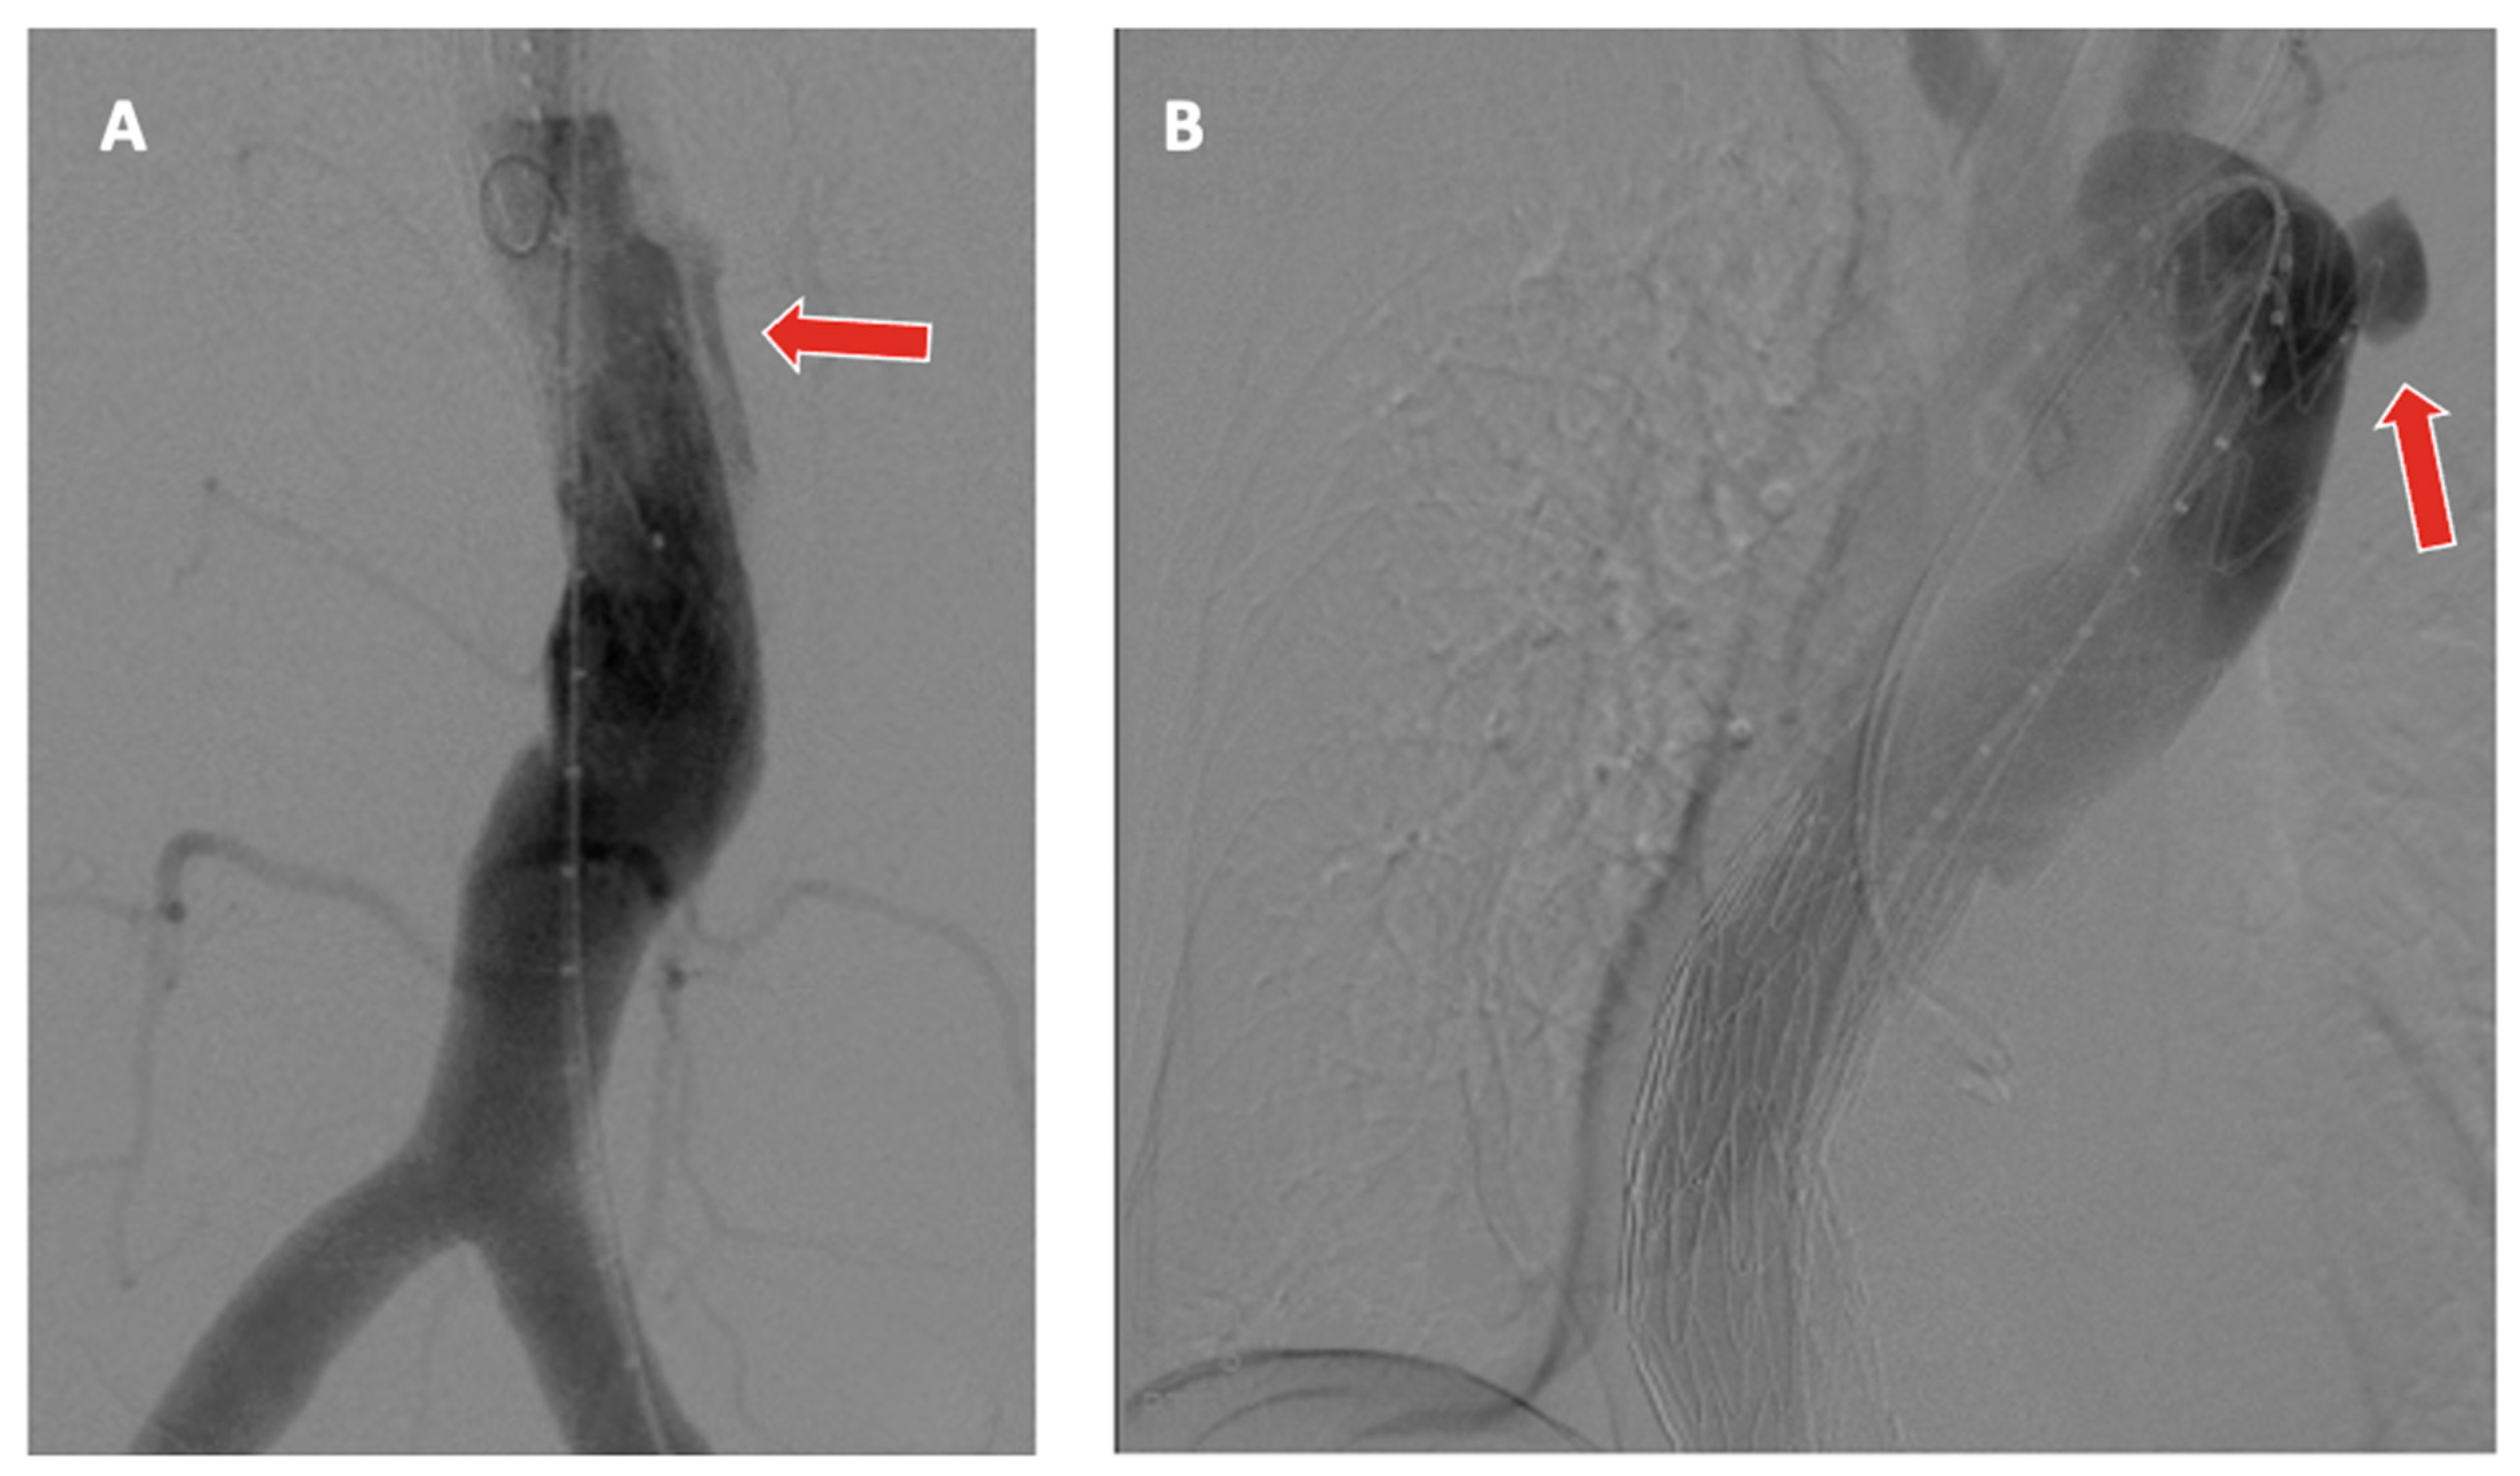

- Gallitto, E.; Faggioli, G.; Spath, P.; Pini, R.; Mascoli, C.; Ancetti, S.; Stella, A.; Abualhin, M.; Gargiulo, M. The risk of aneurysm rupture and target visceral vessel occlusion during the lead period of custom-made fenestrated/branched endograft. J. Vasc. Surg. 2020, 72, 16–24. [Google Scholar] [CrossRef] [PubMed]